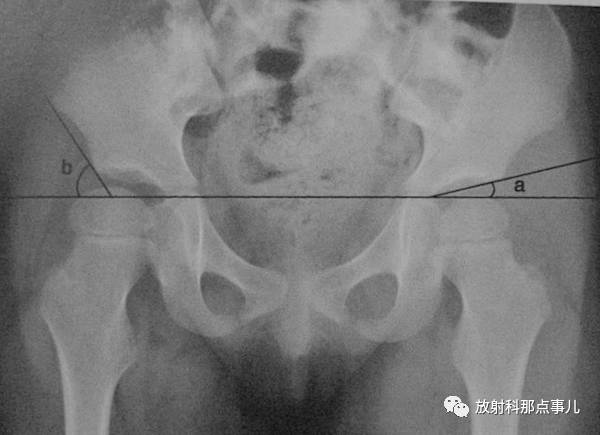

髋臼角

骨盆正位片上,两侧Y形软骨中心连线与髋臼上下缘连线所形成的夹角。正常值新生儿为30° ,1岁以后不应超过25° ,2岁时为20° ,成人为10° 。先天性髋关节脱位时髋臼变浅,髋臼角增大。(上图中角a)

髂骨角

髂前下棘和髋臼外上缘间连线与Y形软骨水平线的夹角。新生儿为55° ,正常值范围在43° ~67° ,角度减小提示异常,如骨质软化症。(上图中角b)